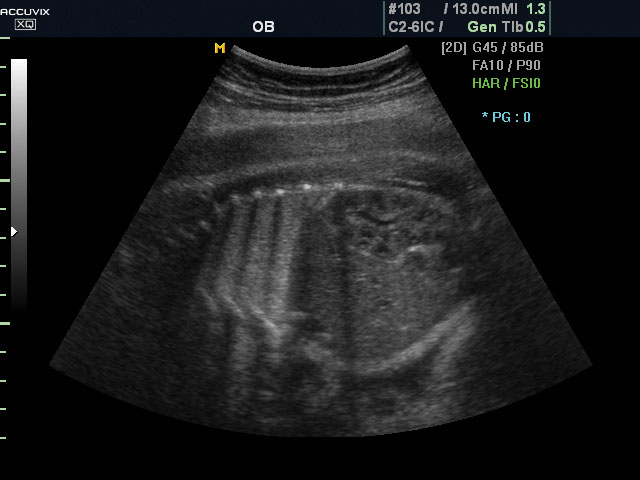

A pontos analízis és diagnózis iránti egyre növekvő igény kiszolgálására a MEDISON egy új real time képfeldolgozó technológiát fejlesztett ki Dynamic MR™ elnevezéssel. Az eljárás a diagnosztikus ismeretanyagot a precizitás és a pontosság egy teljesen új szintjére emeli. Használata az alapvető 2D ultrahang képinformáció real time, kivételesen kristálytiszta és kiemelkedően részletezett megjelenítését teszi lehetővé tűéles kontúrok és finoman rajzolt szövetstruktúra mellett. A DMR™ technológia ideális eszköze az ultrahang-diagnosztikának kezdve a szülészet-nőgyógyászattól a foetalis echon át az általános alkalmazásokig.

A DynamicMR alkalmazása az átlagos ultrahang teljesítményt a zaj és szemcsézettség jellegű műtermékek kiszűrése révén a vizuális diagnosztika, a precizitás és a pontosság új szférájába emeli. Figyelje meg a cerebellum, CSP és cisterna magna élstruktúráit, mennyire pontosan definiáltak és a teljes agyi struktúra ábrázolása a Dynamic MR alkalmazásával milyen látványosan javul.